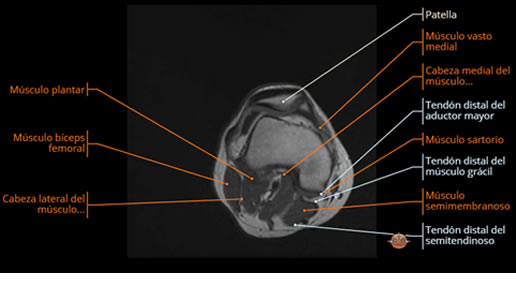

Se realiza estudio de MRI de muslo izquierdo en diferentes planos, con secuencias de Spin Echo, GRE; ponderadas a T1 y a T2, se utilizan pulsos de saturación de grasa y se administra medio de contraste IV a base de Gadolinio en base al peso del paciente.

La diáfisis femoral izquierda muestra reacción perióstica importante, se extiende desde el cuello del fémur, invade trocánteres, diáfisis femoral, medial y distal, es compatible con un proceso infeccioso óseo, el complejo muscular del muslo se ve edematizado.

La resonancia es la modalidad de elección para valorar la extensión intramedular y la infiltración en tejidos blandos, brindando una imagen más detallada del compromiso tumoral. Los hallazgos característicos incluyen:

Lesión de señal heterogénea en secuencias T1 (hipointensa) y T2/STIR (hiperintensa), que refleja necrosis, hemorragia y contenido celular diverso.

Realce intenso y heterogéneo tras la administración de contraste (gadolino), lo que indica vascularización tumoral.

Compromiso de la médula ósea adyacente y de estructuras vecinas, como músculos y neurovasculatura.

Posible presencia de edema óseo y necrosis central.